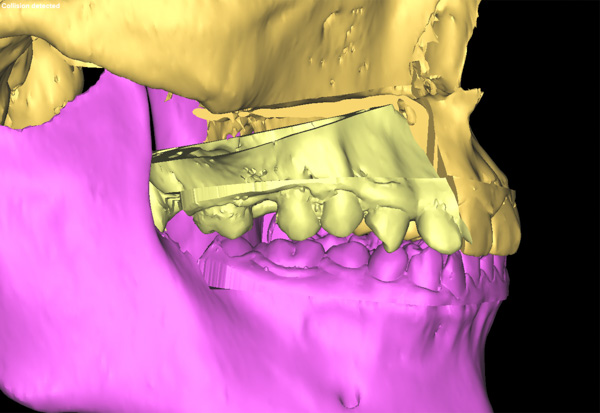

颌面畸形带给患者心理的痛苦是非常严重的,再加上患者正处在最美好的人生阶段,所以手术只许成功,不许失败,所有的环节必须容不得一丝差错。为了能使上颌骨能精确地移动,口腔科专家采用了先进的3D模拟技术制作出了咬合导板,在术前多次模拟重建手术,并向患者展示手术过程,使手术过程达到了最大可能的精准,减轻患者的心理负担。

手术当天,口腔科手术团队首先按照术前设计并3D模拟的截骨导板对右侧上颌骨进行精准分离,按照术前设计的咬合导板精确移动上颌骨达到预定位点,最后精准的使用坚强内固定固位。经过4个小时的努力,完成了正颌手术,待拆除钛板后即可进行咬合关系和对称面型治疗。